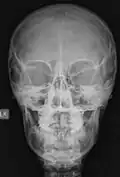

Las imágenes digitales que se adquieren hoy en día, ya sea en radiología digital indirecta (CR) o directa (DR), presentan una gran ventaja debido a la potencialidad que su manejo informático ofrece, en el cual es posible sobre la base de una imagen adquirida aplicar diferentes herramientas como filtros que permiten mejorar el realce de los bordes, suavizar, analizar el histograma y realizar análisis de la calidad de la imagen obtenida. Estas herramientas están disponibles en las consolas de procesado de imágenes de los equipos radiológicos, pero también existen programas dedicados como ImageJ que permiten realizar el análisis de las imágenes, ya sean de uso médico o no. Una de las funcionalidades de ImageJ es la posibilidad de "retocar" la imagen aplicando filtros como los que se observan en las siguientes imágenes en las cuales hemos aplicado a la imagen base de una radiografía de cráneo (al centro) un filtro que permite suavizar la imagen (Imagen 1) y luego a la misma imagen le hemos aplicado un filtro de reforzamiento de los bordes (Imagen 2).

-

Imagen 1 -

Imagen 2 -

Imagen basal